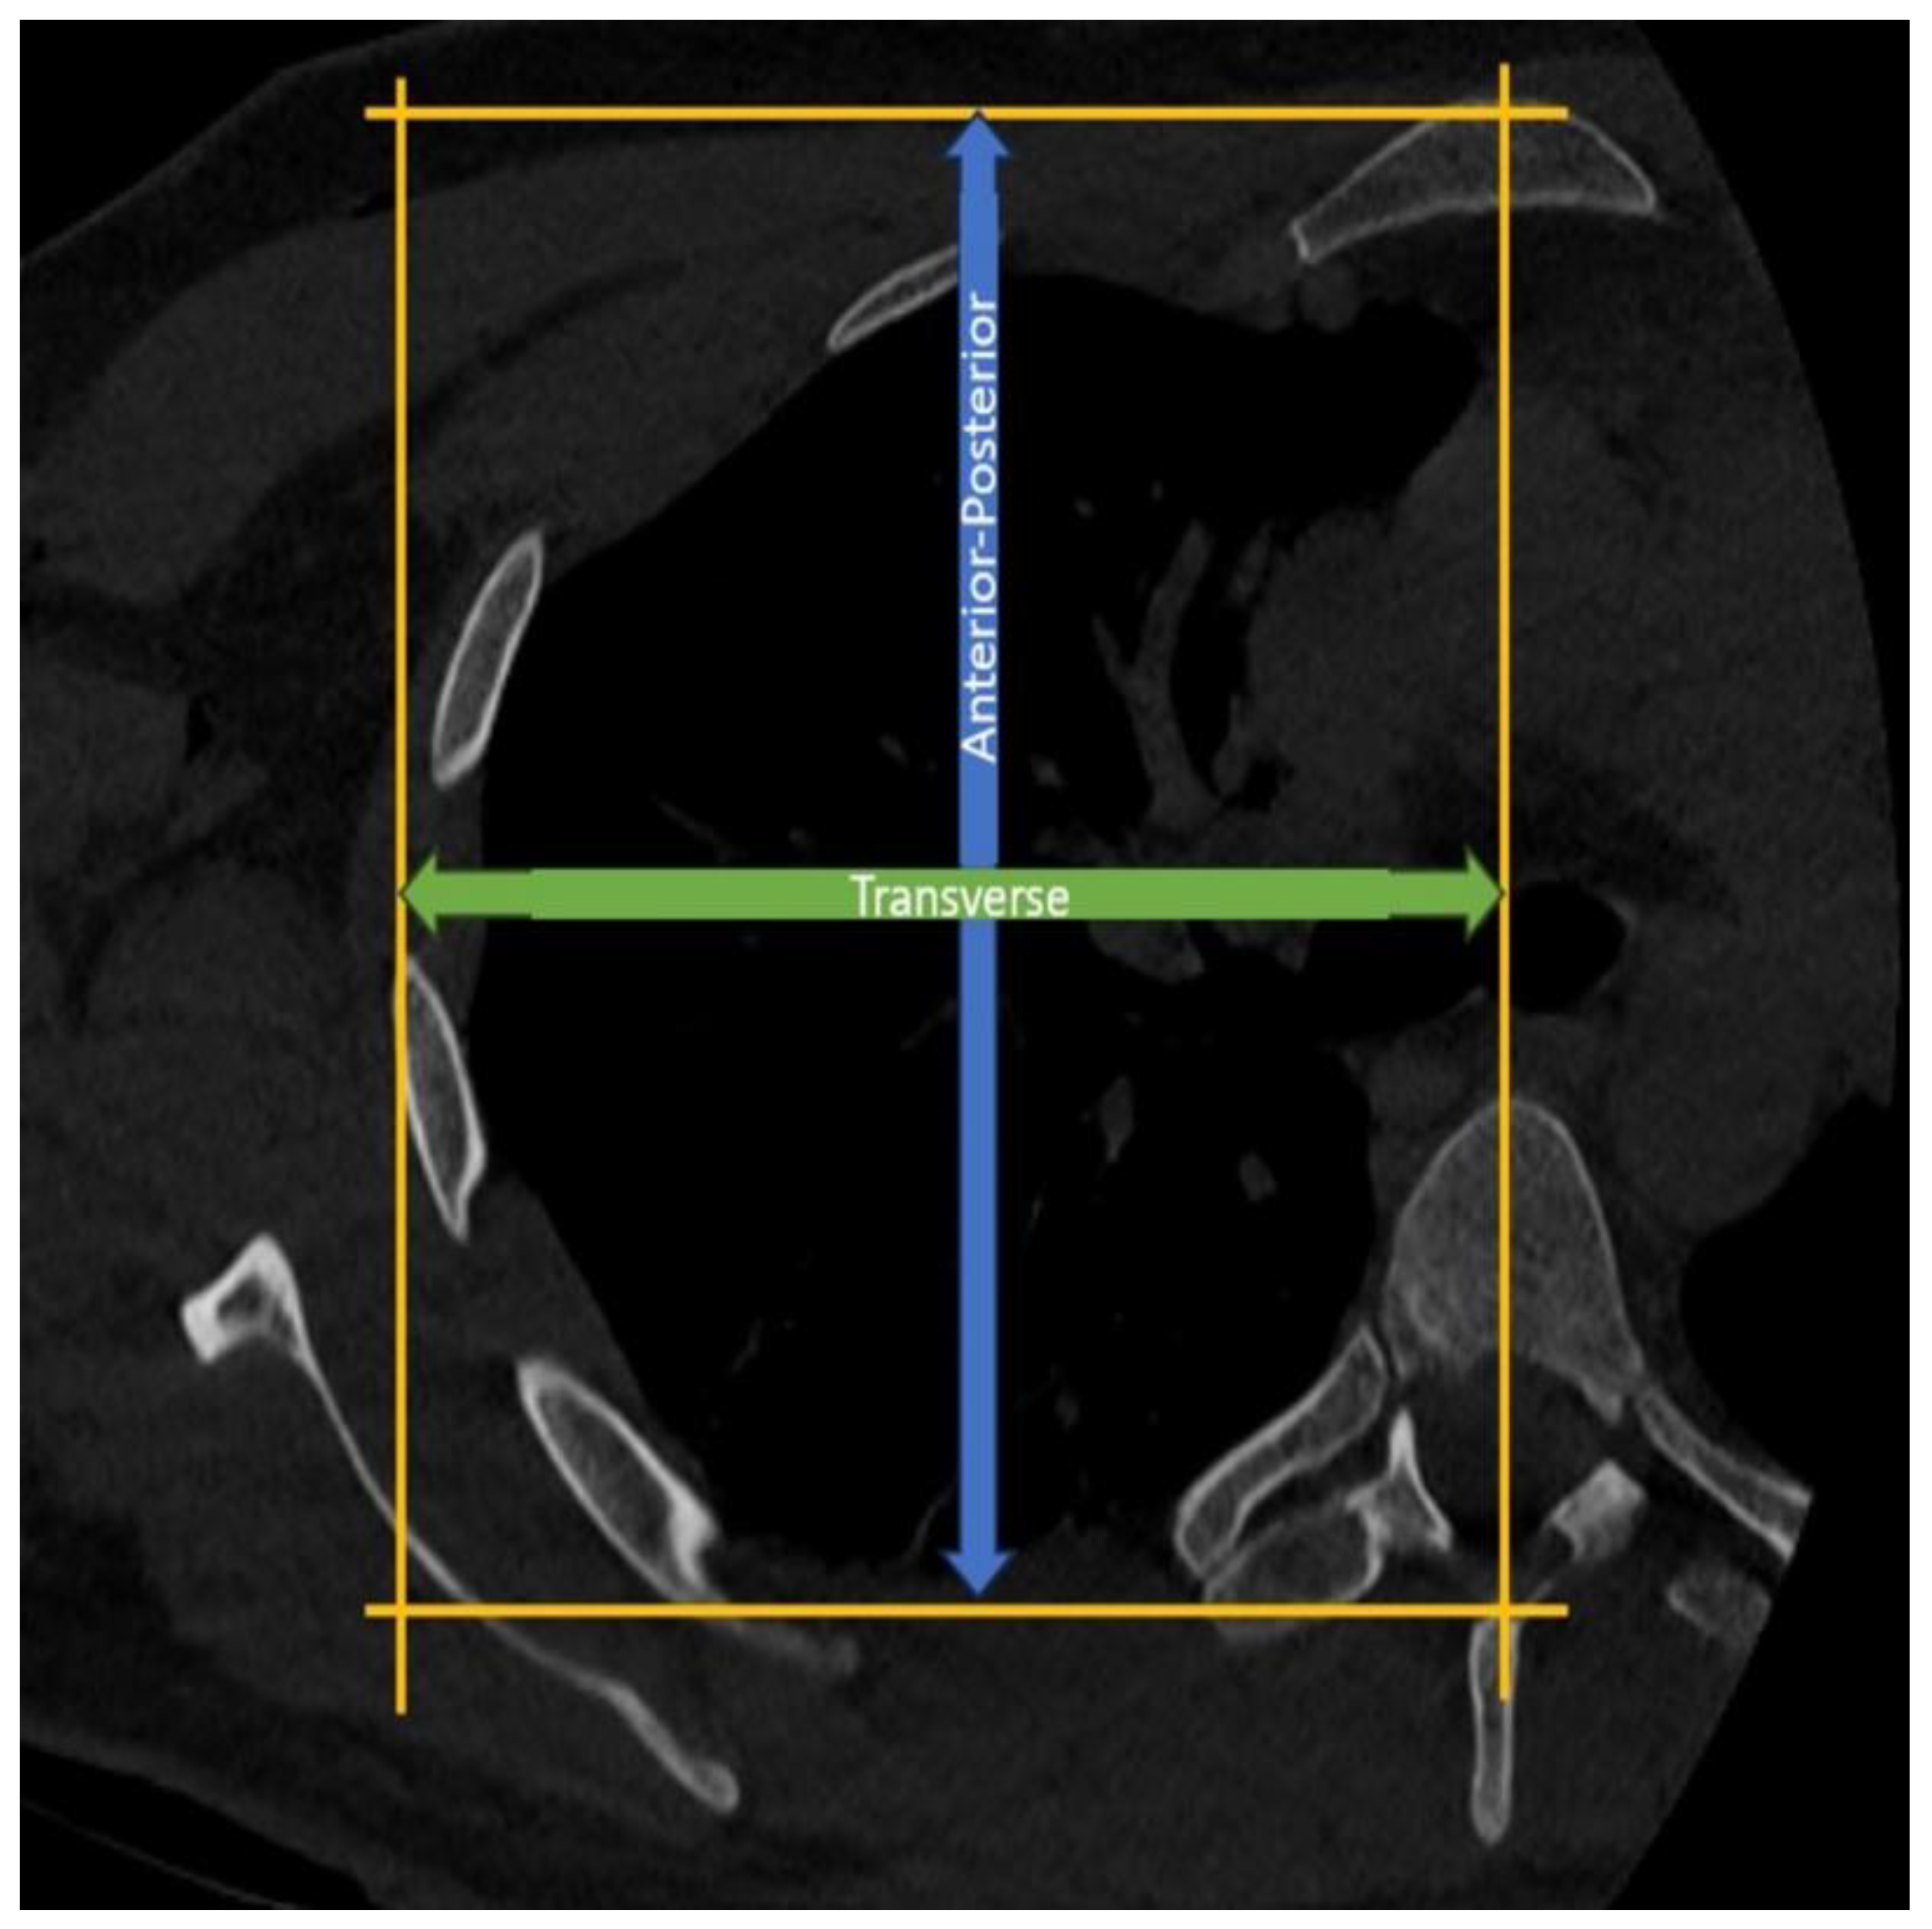

Purpose: This study aimed to determine the relationship between alpha angle (the angle between the screws and the glenoid) and thoracic diameters in patients undergoing the Latarjet procedure. Defining the relationship between thoracic morphology and alpha angle is aimed to fill the gap in the literature to improve surgical outcomes. Methods: This retrospective study analyzed 74 patients who underwent the Latarjet procedure for recurrent anterior shoulder instability between 2022 and 2024. All procedures were performed by the same surgeon using a standardized protocol to ensure consistency of surgical technique across cases. In postoperative chest CT scans, alpha angle, anteroposterior diameter of the thorax, transverse diameter of hemithorax, scapular inclination, and glenoid version were evaluated. Results: The study included predominantly male patients (90%) with a mean age of 26.4±6.4 years who underwent Latarjet procedures predominantly on the right side (60%). Significant associations were observed between thoracic morphology and alpha angle on postoperative CT scans. There was a significant positive correlation between anterior-posterior/transverse diameter ratio (AP/T) and alpha angle (r=0.407, p<0.001), as well as correlations between scapular inclination, glenoid version, thoracoscapular angle, and alpha angle (r=0.275, p=0.018; r=0.241, p=0.039; r= -0.288, p=0.013, respectively). Patients were divided based on an alpha angle threshold of 15 degrees, with results indicating worse outcomes for angles above this threshold. Additionally, the AP/T ratio demonstrated predictive value for poor outcomes (AUC=0.660, p=0.018) with a threshold of 1.2545. Conclusion: This study highlights the direct impact of thoracic morphology on the alpha angle observed on post-Latarjet chest CT scans. Specifically, patients with a higher ratio of anterior-posterior to transverse thoracic diameter (AP/T) show a proportional increase in alpha angle. When the AP/T ratio exceeds 1.25, surgeons may face challenges in achieving the target alpha angle.

| AP/T | 1.22 ± 0.10 | 1.29 ± 0.12 |